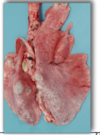

Fibrinous pneumonia

It is cranioventral and may be uni/bilateral